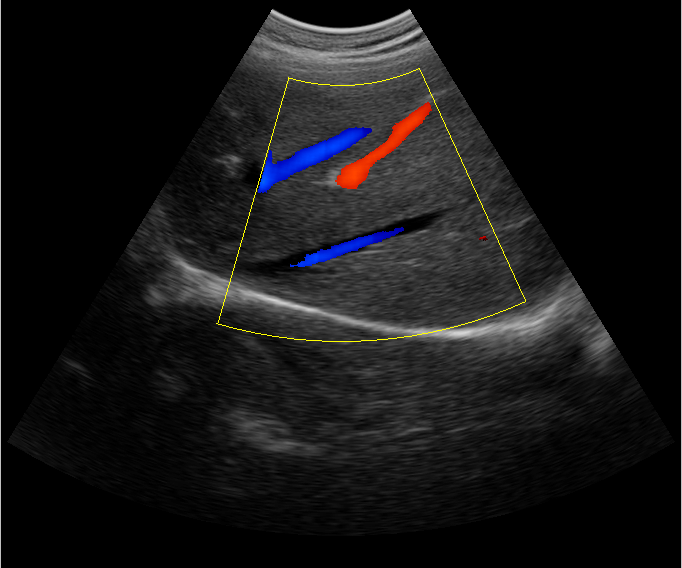

B超檢查主要是檢測(cè)肝臟的外形、大小、膽囊、門(mén)靜脈、回聲粗線等問(wèn)題。由于乙肝病毒造成肝細(xì)胞破損嚴(yán)重,肝細(xì)胞出現(xiàn)問(wèn)題,發(fā)生異常外形就會(huì)改變,通過(guò)B超檢查就能很清楚的檢查出肝臟受損的程度,以及肝臟的大小是否改變,肝臟是否發(fā)展為肝纖維化、肝硬化等。還可以檢查門(mén)靜脈主干內(nèi)徑是否增寬等情況。

肝臟B超還可以通過(guò)肝臟的門(mén)靜脈、回聲粗線、膽囊等指標(biāo)來(lái)診斷病情。由于肝炎病毒長(zhǎng)期侵害會(huì)造成肝細(xì)胞破損嚴(yán)重,肝細(xì)胞出現(xiàn)異常,肝臟發(fā)生異常時(shí)外形就會(huì)改變。通過(guò)肝臟B超檢查就能很清楚地看出肝臟的受損程度,以及肝臟的大小、形態(tài)、回聲等是否正常。有利于肝臟的疾病的正確診斷。